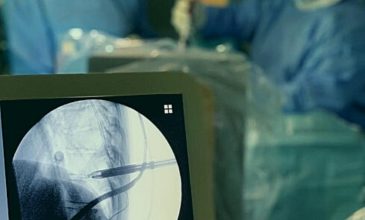

• Ενδοσκοπική ή διαδερμική σπονδυλοδεσία με χρήση ακτινοσκοπικού C-arm, O-arm ή ρομποτικής καθοδήγησης.

Η Ελάχιστα Επεμβατική και Ενδοσκοπική Χειρουργική (M.I.S.S.) αντιμετωπίζει όλες σχεδόν τις παθήσεις της σπονδυλικής στήλης με μικρές τομές δέρματος (~1 cm) και χρήση μικροτεχνικών υπό μεγέθυνση. Έτσι, αποφεύγεται η αιμορραγία και ελαχιστοποιείται η καταστροφή των παρακείμενων ιστών, εξασφαλίζοντας ένα άρτιο χειρουργικό αποτέλεσμα και ταχύτερη ανάρρωση.

• Ενδοσκοπική αφαίρεση κήλης δίσκου και πλαστική του ινώδους δακτυλίου, με στόχο τον περιορισμό του μετεγχειρητικού πόνου.